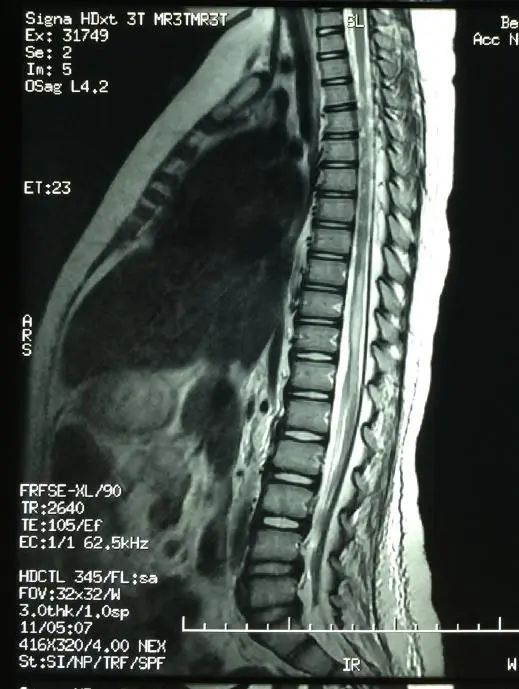

“根据MRI提示胸7~8节段脊髓肿胀坏死样异常信号影,小彩进行了多种相关检查,包括腰椎穿刺脑脊液和血液方面检测,除外了免疫性、感染性、肿瘤性等多种导致脊髓损伤的原因,最终考虑为下腰动作导致的脊髓损伤。”王三梅告诉记者,这种情况属于下腰动作引起的无骨折脱位型脊髓损伤,即在影像学检查上是脊柱无椎体骨折、脱位表现,正因为这种特点,很容易被漏诊、误诊。

▲发生脊髓损伤的MRI图像(供图/王三梅)